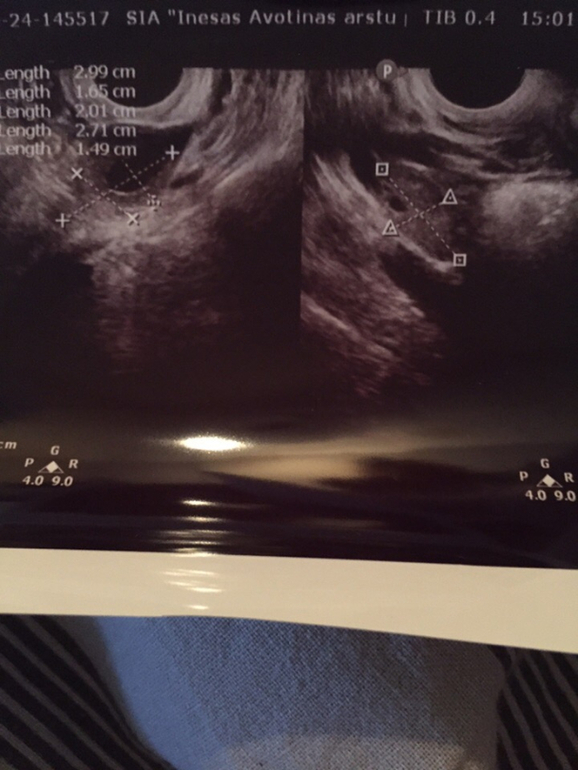

Беременность первая, в 6 недель я ходила на УЗИ, просто чтобы подтвердить маточную беременность. Но врач немного посмотрев, сказала, что возможно их там 2. Она сказала, что одного точно видит, а второй пока не на 100%, но пузырек увидела. Ни про сердцебиение, ни про желтый мешочек, ничего не говорила. А я как то и расстерялась, да и не знала, что вообще спрашивают в таких случаях. Сказала повторить узи через две недели, но время тянется безумно долго. У моего отца есть братья(только я не уверена, близнецы или двойня, не общаемся давно) + у отца парня тоже должны были быть братья близнецы, но закончилось печально. Получается, что шанс есть?Решила спросить тут:)Может кто-то сталкивался с таким, или хоть немного разбирается в снимках:)

P.S один пузырек определился на срок 6недель и 1 день, второй на 5 недель и 6 дней. Там на двух последних снимках будет написано наверху слева, а так же размер пузырьков)

P.S.S Если не ошибаюсь, она сказала что тот, что 5недель и 6 дней и есть эмбрион, но что тогда может быть тот, что на 6недель+1?я окончательно запуталась😢